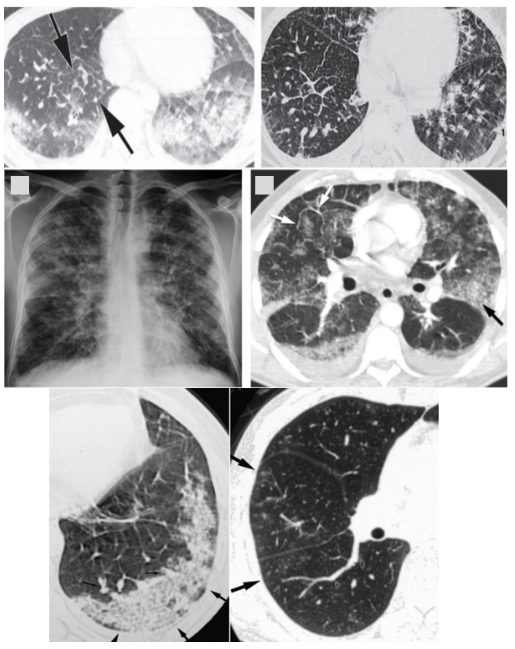

IAEP影像学表现为双肺弥漫的磨玻璃影,可伴有小叶间隔增厚,也可能出现实变和胸水。ICEP影像学表现为经典的反肺水肿征象,外周分布的实变,有机化性肺炎的影像学特点。

图片

IAEP影像学表现

图源:Eur J Radiolm 2008, 65(3):462-467. Radiol Clin North Am, 2016, 54(6):1151-1164. Radiographics, 2007, 27(3):617-37; discussion 637-639.